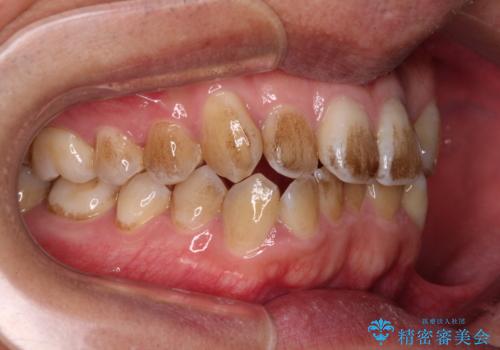

- 前歯のデコボコを気にして来院された患者様です。

極力費用を抑えた上で、自己管理の煩わしの少ない装置を希望とのことで、メタルブラケットによるワイヤー矯正を選択されました。

舌の突出癖があり、デコボコが解消される際に出っ歯傾向になる恐れがあるため、舌のトレーニングを行っていただきながら、矯正治療を進めていくこととしました。